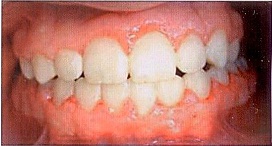

В течение 5-ти месяцев использования межчелюстной тяги динамика коррекции окклюзии по сагиттали слабоположительная. Кооперация с пациентом и его родителями ухудшилась, у мальчика значительно ухудшилась гигиена, межчелюстную тягу носил недостаточно, поэтому этап коррекции по сагиттали и вертикали оказался затруднен. Родители стали настаивать на снятии аппарата, т.к. положение передних зубов их устраивало, а смыкание в боковых отделах их не интересовало (рис. 4-6).

Рис. 4

Рис. 5

Рис. 6

В результате 12-месячного ортодонтического лечения нам удалось успешно провести лечение экструзиоинного вывиха верхних резцов. Верхние резцы заняли правильное положение относительно нижних, их перекрытие составило примерно 2,5-3 мм. Но сагиттальные взаимоотношения по-прежнему соответствуют III классу Энгля и сохранились бугровые окклюзионные взаимоотношения. На ОПТГ и прицельной рентгенограмме зубов 1.1.,2.1 и 2.2 периодонтальная щель сохранена на всей протяженности корней. Наблюдается небольшая апекальная резорбция верхушек корней 1.1,2.1 и 2.2 зубов.

В качестве ретенции зафиксированы несъемные flex-ретейнеры на зубы 1.3 - 2.3 и 3.3 - 4.3 на неограниченный срок [2]. На нижний зубной ряд изготовлен съемный ретейнер Hawley, назначено ношение в течение 14-16 часов в сутки. Осмотр через 6 месяцев, затем 1 раз в год до окончания скелетного роста.